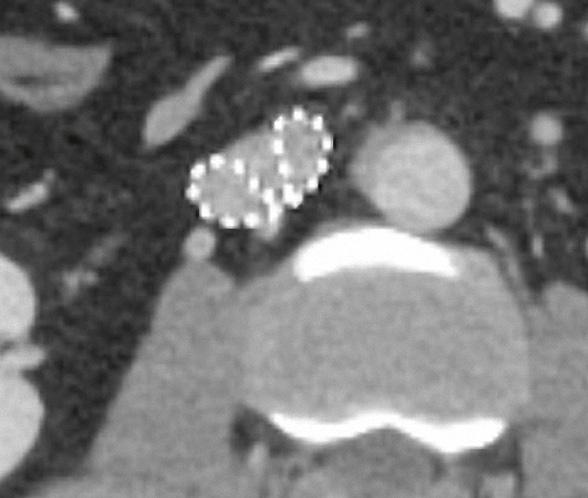

Portalvenöse Abdomen-CT. Auch hier ist die Dosis am Aquilion Prime SP mit AiCE geringer, zudem auch hier geringeres Bildrauschen mit sehr guter Abgrenzbarkeit beispielsweise von Leberläsionen.

Portalvenöse AbdomenCT, Canon Aquilion ONE, Rekonstruktion: AiDR 3D; DLP 304,9 mGy × cm/ 5,5 mSv

Portalvenöse AbdomenCT, Canon Aquilion Prime SP, Rekonstruktion: AiCE; DLP 221,5 mGy × cm/ 4,0 mSv